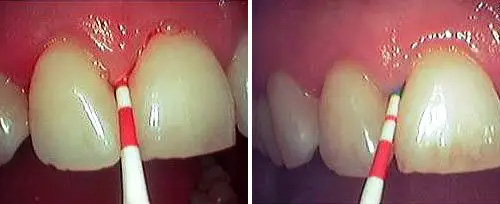

Closed Curettage